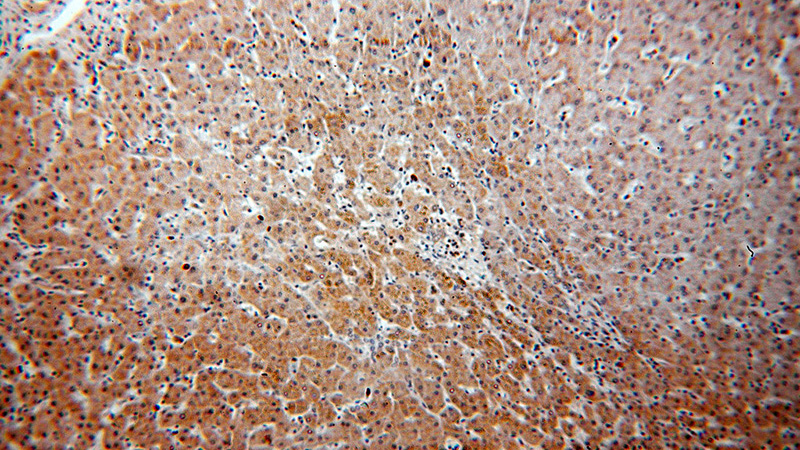

Immunohistochemical of paraffin-embedded human hepatocirrhosis using Catalog No:109706(CYP4F11-Specific antibody) at dilution of 1:50 (under 10x lens)